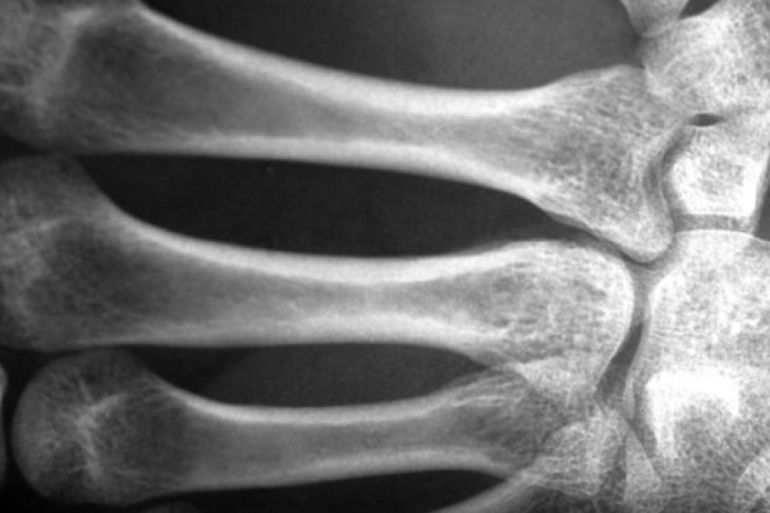

تقدّر المؤسسة الوطنية لصحة العمود الفقري في الولايات المتحدة أن مليوني رجل مصابون بهشاشة العظام، المرض الذي يعني أن تصبح العظام مسامية وتفقد تدريجيا كثافتها وقوتها، مما يعرّض الأفراد لخطر أكبر للإصابة بكسور العظام، حتى من السقوط البسيط.

ويعاني 16 مليون رجل من انخفاض كتلة العظام (osteopenia) وهي حالة تنخفض فيها كثافة المعادن في العظام عن القيم المرجعية الطبيعية، لكنها ليست منخفضة بما يكفي لتتوافق مع معايير تشخيص هشاشة العظام.